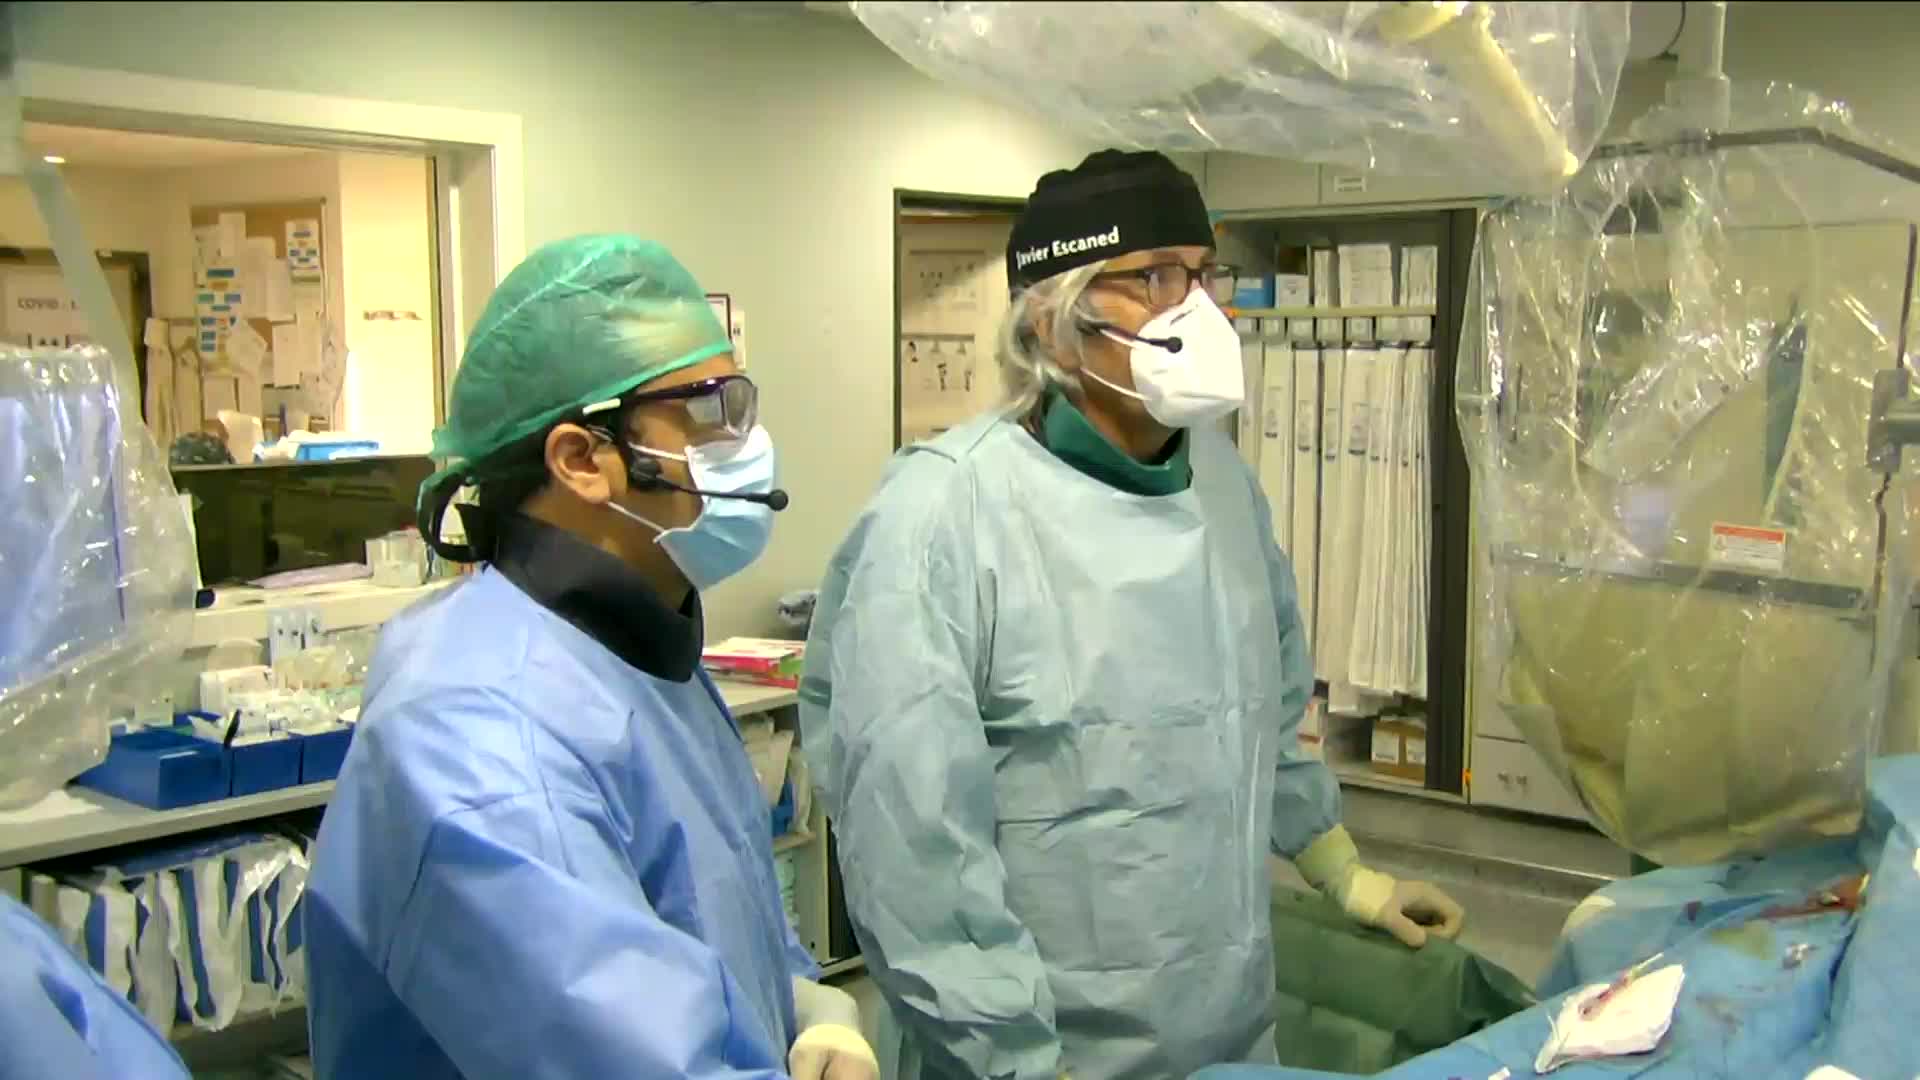

Best practices and personalised medicine in complex PCI - Prof Javier Escaned